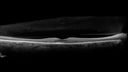

51 year old female on with trouble driving at night for a year. No eye examination for several years. 2009 (11 years ago) Plaquenil 300 then up to 400 a few years ago now down to 300 - 5'2" 135 lbs

VA 20/20 OD, 20/25 OS